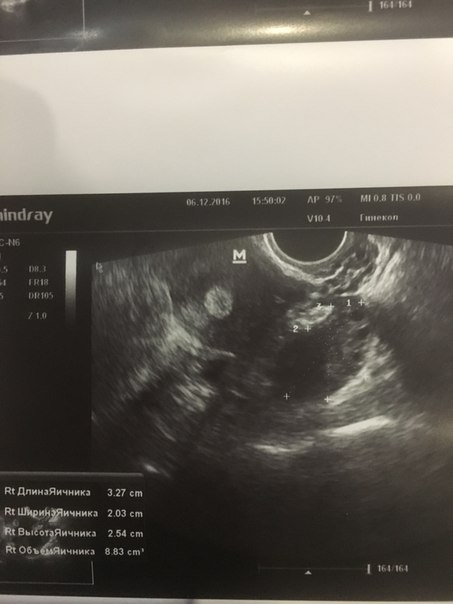

Помогите кто нибудь.Нет деток и никакого аборта ни викидыша ничего 5 лет.живу с мужем.мне 22.все эти 5 лет по врачам по больницам.в сентябре была чистка.на днях на УЗИ .сказали все плохо срочно что то делать иначе климакс в 23 года.что делать неужели это конец приложу результаты УЗИ и гормонов.может кто сталкивался.поделитесь

Я 6 шт фолликов насчитала в яичнике, очень хороший эндометрий,при чем тут климакс ( странный доктор)??? Проблема в гормонах, снижайте пролактин и рожайте на здоровье)))

Они не лопаются и не созревают.доктор говорит что яичники спят и не работают.кровотечение по месяцу идет из за поликистоза.жду анализа на оставшийся резерв фолликулов.так как она говорит что яичники пусты лишь железистая ткань

Так мне и сказали что яичники пустые не работают.Овуляция не происходит.

Гормоны вообще не про климакс, а наоборот - соотношение и тестостерон в пользу СПКЯ, но пи этом яичники на УЗИ не поликистозные. Я бы Вам рекомендовала сдать АМГ, ЛГ, ФСГ еще раз,, еще раз пройти УЗИ , сдать кровь на глюкозу и инсулин. Немного сумбурно все написали. Если нужна будет помощь, напишите все подробно, можно ко мне в группу.

Да поставила поликистоз